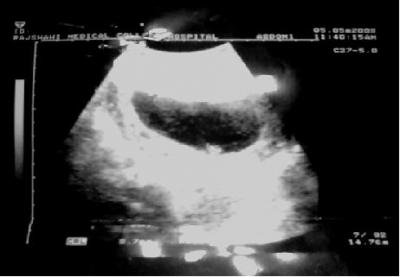

পরের সপ্তাহে দেখা করতে গেলে পুরোন চেকাপগুলোর সাথে আমাকে আল্ট্রাস্নোগ্রাম করতে বললো তারা। ওদেরই রেডিওলজি বিশেষজ্ঞের কাছে রেফার্ড করা হলো আমাকে।

আজ ওদের আচরণ আমার খুব একটা স্বভাবিক লাগলো না। কারন ওদের ব্যাবহারে আজ আন্তরিকতার অভাব ছিলো। আধা ঘন্টার মধ্যে আল্ট্রাস্নোগ্রাম করালাম এবং সাথে সাথে রিপোর্টও রেডি করে দিলো ওরা। আমাকে বললো বিশেষজ্ঞ ডাক্তারের সাথে কথা কথা বলতে।

Uterus সম্পর্কে রিপোর্টে লেখা ছিলো

Gravid Uterus containing gestational sac.

Fetal cardiac activity is absent.

ভাষা গুলো একটু কঠিন হলেও রিপোর্টে ডাক্তাররা এরকম ভাষায় ব্যাবহার করে থাকেন। মনে হয় কিছু ছাড়া-ছাড়া শব্দ। এর মানে বের করার জন্য আমাকে ডিকশনারী খুলে বসতে হবে না। এর মানে হলো__

জরায়ূটি শুধু মাত্র একটি মাংশ পিন্ড ধরে আছে।

ভ্রূণে হৃদস্পন্দনজনিত সক্রিয়তা অনুপস্থিত।

[নারী মনকে বোঝার জন্য লাকী আল মামুনকে অনেক অনেক ধন্যবাদ। তার প্রথম সন্তান হারাবার বেদনা থেকে এই গল্পটি লেখা। গল্পে ব্যাবহৃত ছবিটি লাকী আল মামুনের নিজের আল্ট্রাস্নোগ্রাফীর ছবি। যেটিকে ডাক্তাররা শিশু বলে কখোনই স্বীকার করেন নাই।গল্পটি নেতিবাচক দৃষ্টিকোন থেকে লেখা হয়েছে; এর জন্য আমি তার কাছে আন্তরিক ভাবে ক্ষমা প্রার্থী। লেখার সময় কাল ২০০৮]